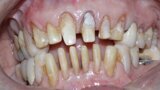

Figure 1 Close up smile before treatment